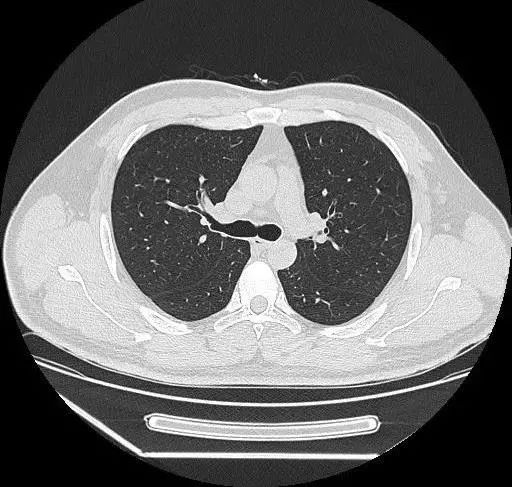

生病了经常会到医院就诊。当出现某些症状比如长期咳嗽,或者咳血,或者剧烈咳嗽伴发热等情况,医生为了明确病因,会叫病人进行CT检查。细心的患者心理会产生一个问题:

根据临床研究报告,一次CT检查的辐射剂量约为8-10mSv!

由此可见,每年1-2次的CT检查,完全在安全的辐射剂量范围内。而每次胸片的辐射剂量大约为0.025mSv,对人体的影响相当于3天的本底辐射水平,影响微乎其微。

原则上来说,短期内最好不要反复进行CT检查。但有些患者身患严重疾病比如肿瘤、重症肺炎、咯血、气管内异物、张力性气胸等情况,医生为了及时准确治疗,需要反复进行CT检查判断病情。这时,相对于辐射对人体可能的伤害,延误疾病诊断和治疗的危害更大。两害相遇取其轻!因此作为患者及家属对这种短期内必要的CT检查不应当拒绝,否则有可能延误疾病的治疗,对自身造成更大的伤害,甚至危及生命。